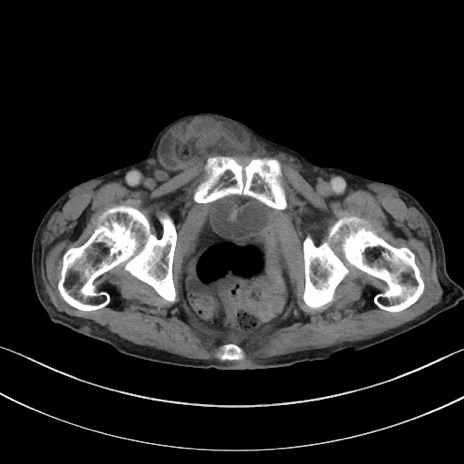

【症例】 70歳代男性

【主訴】右鼠径部腫瘤、疼痛

【現病歴】本日朝より上記主訴あり、受診。

【既往歴】膀胱癌にて膀胱全摘、両側尿管皮膚瘻

【データ】WBC 5600、CRP 0.56